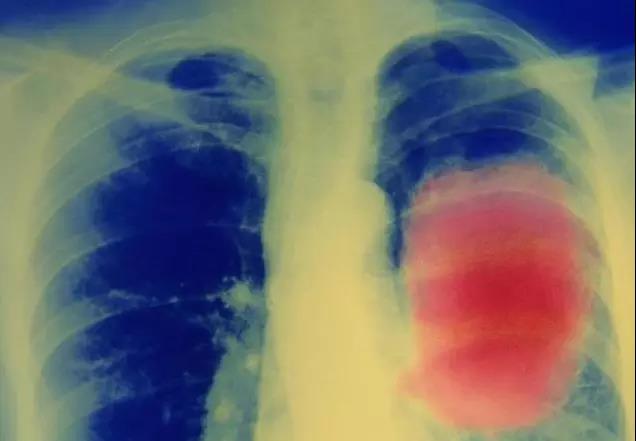

到目前为止科学家们对于癌症干细胞扩张过程中所需要的代谢途径仍了解不足,但对该问题的研究将有助于开发新的治疗手段。近来自美国乔治城大学医学中心的研究人员发现了癌症干细胞的一个代谢弱点,并找到特异性靶向药物或可帮助提高传统治疗药物的效果。

相关研究结果发表在国际学术期刊Cell Death & Differentiation上。